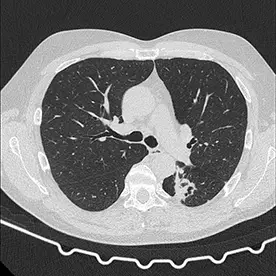

In der angefertigten CT des Thorax und Abdomens zeigen sich zwei große Lungenherde mit teils diffusen Verkalkungen und kleinen Kavernenbildungen im apikalen Ober- und Unterlappen links (Bild 1 und 2). Da es sich um eine ausgeheilte Infektion zu handeln scheint, kann man hier von einem Simon-Spitzenherd sprechen.